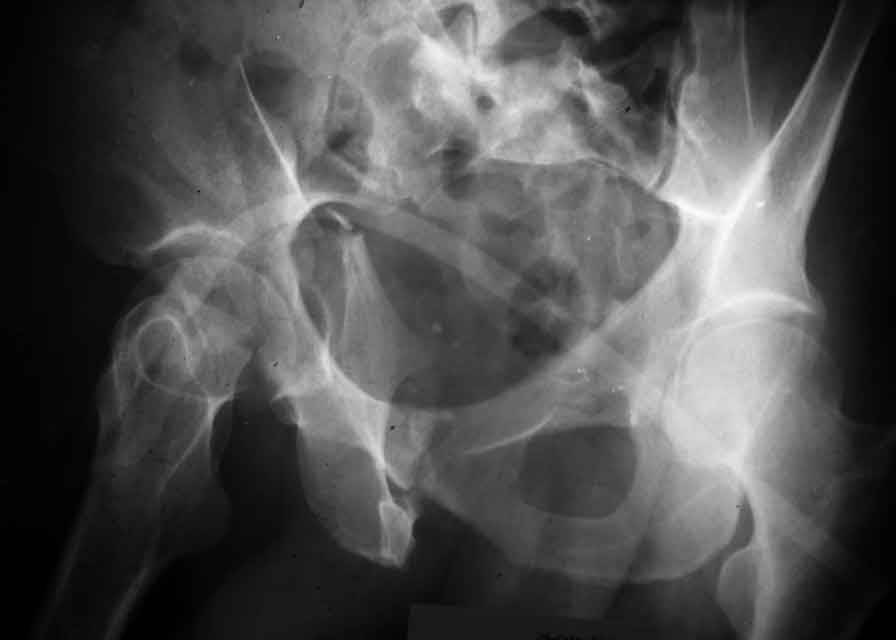

Dear Friends This is a 57 y old male.

Your input is welcome as to the classification of this fratcure, as well as the proposed management.

Dear Sir it looks quite difficult classify this fracture because the iliac view is not so clear.

In my opinion it is a column fracture because the obturator foramen is interrupted. There is a fracture of the posterior wall. If we assume the ap view as an iliac view it could be an anterior comun fracture plus posterior wall. It is difficult also to judge the head of the femur.

From the x rays it appears like a bicolumnar fracture with iliac extension (AO C1).